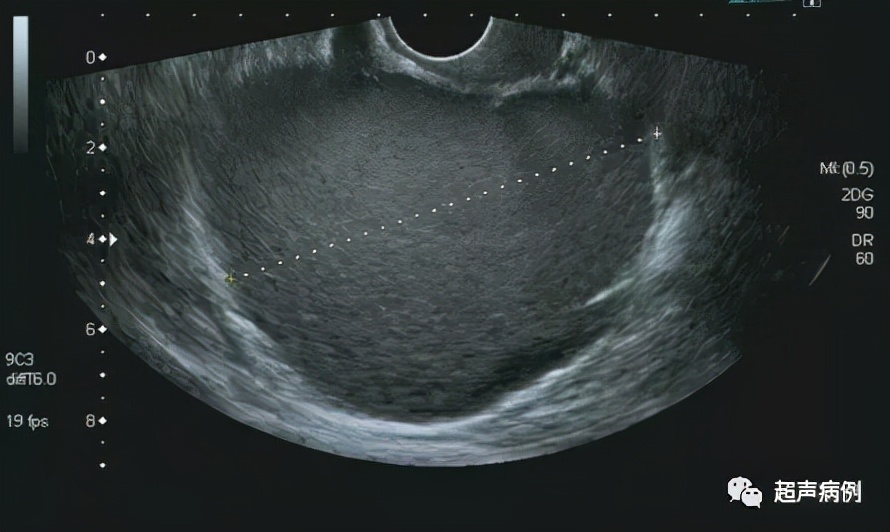

在子宫后方盆腔内查见一约10.4x9.7x7.3cm无回声区

形态规则,边界清楚,内透声差,呈毛玻璃样改变

内可见强回声分隔

CDFI:该无回声区内部及周边未见明显血流信号。